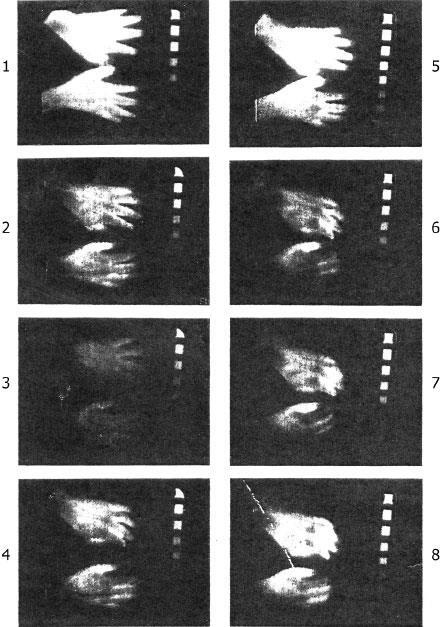

![]() Рис. 2. После приема 5, 10 или 15 граммов триптофана (отмечено стрелками) никакого улучшения не наблюдается. (На шкале ординат — SP — парадоксальный сон — ПС; SL — медленный сон — МС) ![]() Рис. 3. Восстановление сна после приема 1500 мг DL 5-HTP (5-окситриптофана) в 23 часа и 4 часа (стрелками). — SP — парадоксальный сон — ПС; SL — медленный сон — МС; Е — бодрствование (Б). Наблюдалось восстановление парадоксального сна после второй дозы 5-окситриптофана. Стадии сна: I, II, III и IV. Парадоксальный сон — SP. По шкале абсцисс: время (в часах). ![]() Рис. 4. Кумулятивная диаграмма продолжительности сна (в минутах) за каждые 10 минут в течение 16 последовательных ночей. Стрелки указывают моменты приема больших доз DL 5-HTP (23 часа и 4 часа). Жирная линия — стадии II, III и IV. Закрашенные участки — парадоксальный сон. Тонкая линия — стадии II, III и IV под воздействием плацебо, которое больная принимала 16 ночей в то же время, что и DL 5-HTP. Таким образом, эта молодая женщина принадлежала к группе «малоспящих» (short sleepers), описанных Джонсом и Освальдом в 1968 году. ![]() Рис. 5. Термографическое исследование процесса длительного галлюцинаторного эпизода (галлюцинаторного дистальгического синдрома) (Д-р Шмитт, лаборатория термографии, больница Эдуарда Эррио, Лион). № 1: контроль. № 2: появление болей в конечностях. Испытуемый сжимает одной рукой другую. № 3: Глаза закрыты. Испытуемый разговаривает с воображаемым собеседником. Регистрация ЭЭГ демонстрирует бодрствование. № 4: длительная галлюцинация. № 5: возвращение в нормальное состояние. Испытуемый открывает глаза. № 6 и № 7: пациента просят закрыть глаза. У него снова начинаются галлюцинации. ЭЭГ бодрствования. № 8: очень сильная стимуляция возвращает пациента к реальности. Завершение галлюцинаторного эпизода. Испытуемый отчитывается о сновидении. Экспериментальная депривация сна